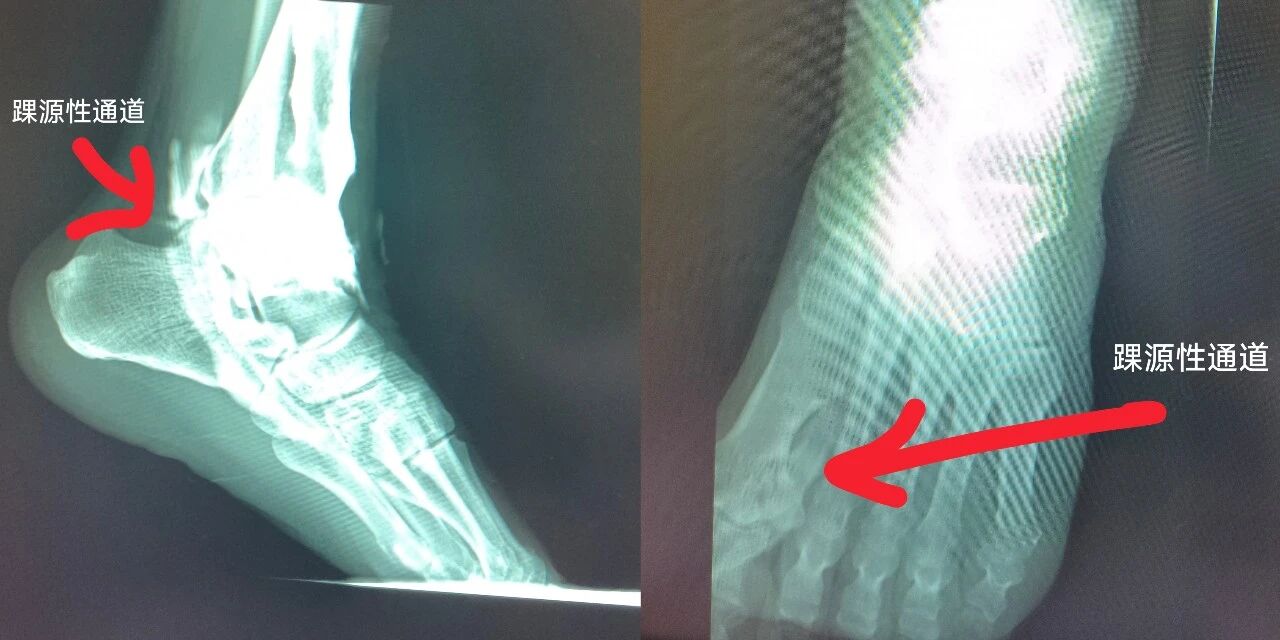

术前“造影追踪”,锁定漏水通道

术前,张平平与副主任医师陈文忠、主治医师徐泽进行了认真的病例讨论,认为患者囊肿病因不在脚趾,在踝关节。于是为患者在造影室做了“踝关节腔造影+动态透视”检查。当造影剂缓缓注入关节腔后,屏幕上清晰显示:显影药液顺着踇长屈肌腱鞘一路“跑”到脚趾囊肿里——交通口被精准定位。“能够确认这就是踝源性囊肿。”张平平说,如果缺少“溯源确诊”这一步,手术只能做一次“表面文章”。